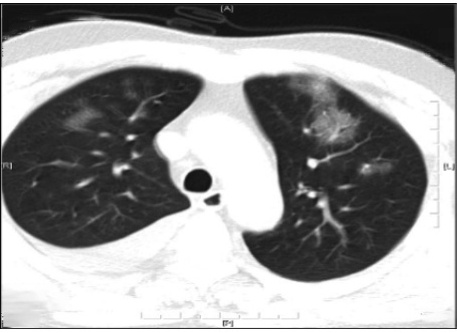

警惕,无明显危险因素的甲流患者也可发生急性呼吸窘迫综合征!

病史摘要:52 岁女性,主因严重突发性呼吸困难、胸部不适、咽喉疼痛就诊。就诊前一周有流涕、咳嗽等症状,前一天因咽喉疼痛加重就诊,甲型流感阳性,对症治疗及用奥司他韦后出院。既往有血脂异常、偏头痛、两年前轻微创伤性颅内出血(保守治疗无后遗症)。 诊疗过程:此次就诊呼吸急促、心动过速、血氧饱和度下降,听诊双侧进气良好伴弥漫性干啰音。动脉血气提示呼吸性碱中毒和缺氧,胸部 X 线和 CT 显示双侧斑